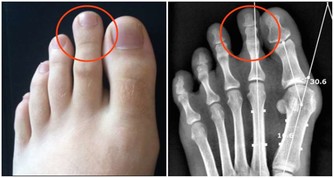

由糖尿病、甲狀腺功能減退或高鈣血症造成的代謝紊亂也會引起便秘。結腸癌會引起何種病症呢?有可能是便秘,也有可能是腹瀉。

糞便在進入結腸前,是一種粘稠的液體,可以在比較狹窄的區域內流動。

隨著結腸蠕動吸收其中的水分,糞便會變得更加濃稠,流動性會逐漸減弱;

腸癌患者體內的腫瘤會阻塞腸道,妨礙糞便通過,進而導致便秘。